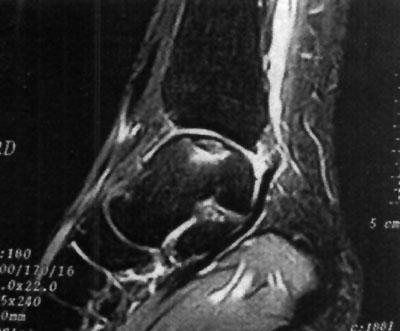

Foto 5: Lesión o.C. visualizada en RMN

La clasificación a partir de imágenes radiológicas mostró un coeficiente de correlación de Spearman de 0,77 (p=0,001) con respecto a la clasificación realizada a partir de imágenes tomográficas, en tanto que el mismo coeficiente entre las imágenes de TAC y RMN fue de 1 (p < 0,001). Esto implicaría una alta correlación entre la clasificación de TAC y RMN mientras que existiría una menor correlación entre Rx y TAC. En relación a los hallazgos de resonancia magnética, 12 pacientes (29,3 %) presentaron un GI, seis pacientes (14,6 %) presentaron un Gila, siete pacientes (17,1 %) un Glib, trece pacientes (31,7 %) un GIII y tres pacientes (7,31 %) un G IV. (fotos 6 a 10) Dieciocho pacientes (43,9%) fueron tratados en forma conservadora y 23 pacientes(56,1%0) fueron tratados en forma quirúrgica. (Ver tabla 4)

Foto 8: Lesión GII b

Foto 9: Lesión GIII

Foto 10: Lesión G IV